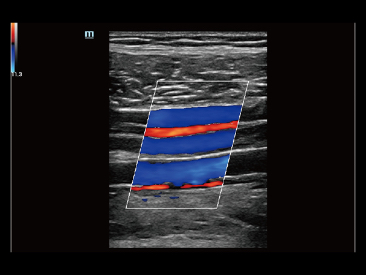

As well as the premium level image quality, Resona 7 also enhances clinical research capabilities with the revolutionary V Flow for vascular hemodynamic evaluation, and the most intelligent plane acquisition from 3D datasets for fetal CNS diagnosis. Combining the most intuitive gesture-based multi-touch operation and all the essential clinical features, Resona 7 is truly leading new waves in ultrasound innovation.